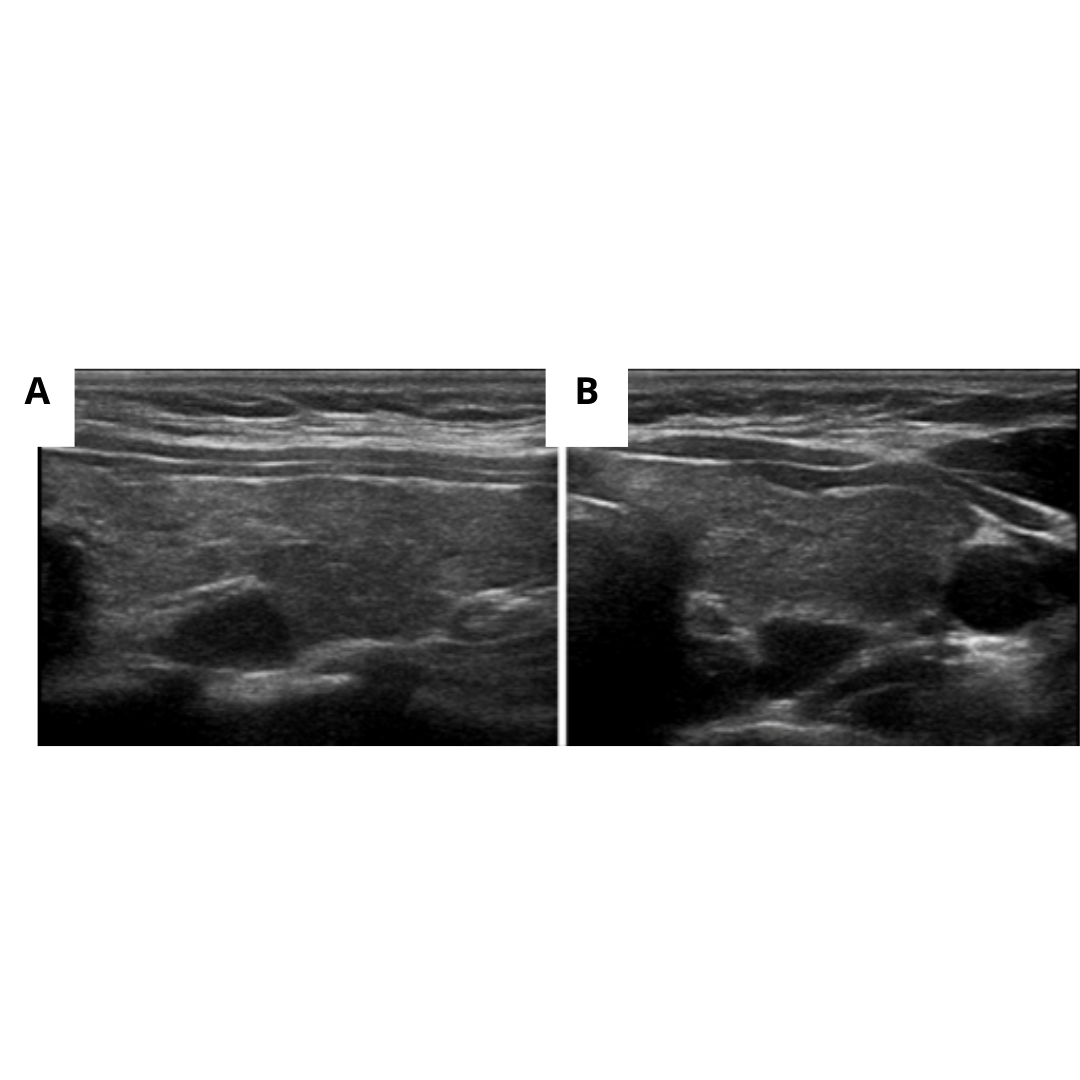

La hiperplasia de paratiroides es la segunda causa más frecuente de HPT. Se considera hiperplasia cuando existe más de una glándula aumentada de tamaño; esto significa que bajo ecografía se observará más de un nódulo con características ecográficas de adenoma (figura 6).

Figura 6: Hiperplasia de paratiroides: Ecografía muestra múltiples lesiones nodulares redondeadas/ovaladas, hipoecogénicas y con flujo Doppler interno (flechas), localizadas en borde posterior de ambos lóbulos tiroideos.